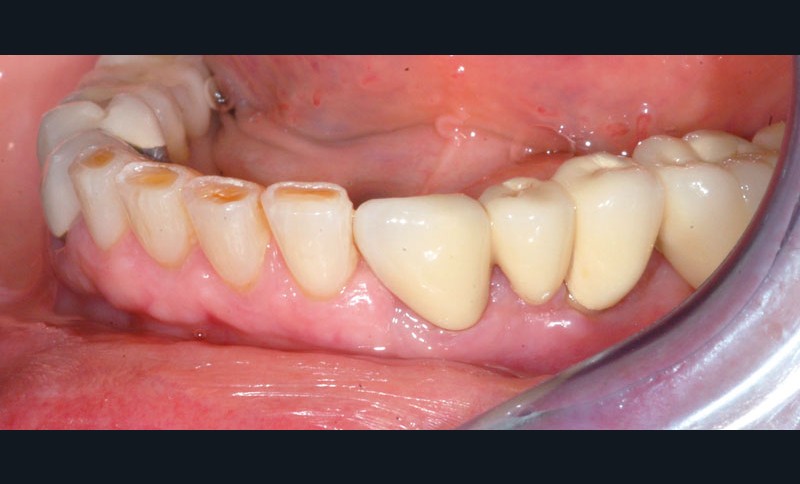

Après dépose du bridge mandibulaire et reprise du traitement endodontique, un bridge transitoire est réalisé à partir du wax-up. Une empreinte de celui-ci est faite avec Imprint™ 4 Preliminary Penta™ (3M ESPE).

L’automoulage est garni avec une résine composite (Protemp™ 4, 3M ESPE), avant ajustage et finition (roues spirales Sof-Lex™, 3M ESPE), pose du bridge transitoire.